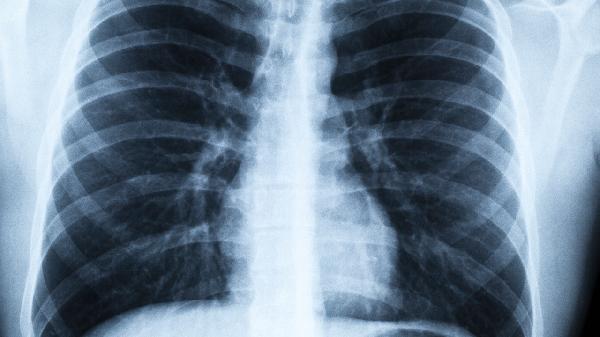

尘肺患者日常需多食银耳、山药等白色养肺食材,避免接触粉尘环境。八段锦"调理脾胃须单举"和"左右开弓似射雕"两式每日练习20分钟,能增强膈肌力量。重度尘肺出现持续咯血或呼吸困难时,需立即就医进行支气管肺泡灌洗等西医治疗。中药调理期间每月复查胸片,观察病灶变化情况。